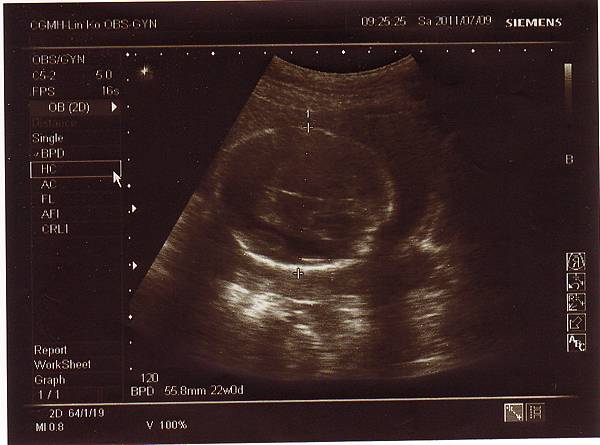

兩個星期後,也就是今天2011.07.09回診了,

還好一切順利,寶寶健健康康的,

醫生說是個長腿妹妹,心跳強而有力,

兔小妹的手掌~

我是兔小妹的象徵喔!